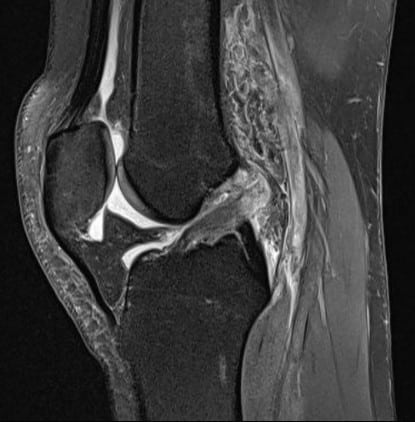

Imatge generada mitjançant la RMN d’un genoll

Un dels reptes principals en medicina esportiva de l’alt rendiment és augmentar la precisió diagnòstica en lesions musculars, articulars i òssies, així com fer un seguiment més exhaustiu i individualitzat de l’evolució de cada esportista per així optimitzar els temps de recuperació.

- Cicatrització muscular en lesions esportives: estudis basats en ressonància magnètica que analitzen els processos de recuperació muscular i proposen classificacions a partir de l’experiència clínica acumulada. Aquests resultats contribueixen a millorar la presa de decisions en les fases crítiques de la recuperació.

- Predicció del retorn a la competició: investigacions orientades a identificar, a partir de les proves d’imatge, indicadors que permetin anticipar el risc de recaiguda. Aquesta informació complementa l’avaluació clínica i facilita la presa de decisions sobre el retorn a la competició.